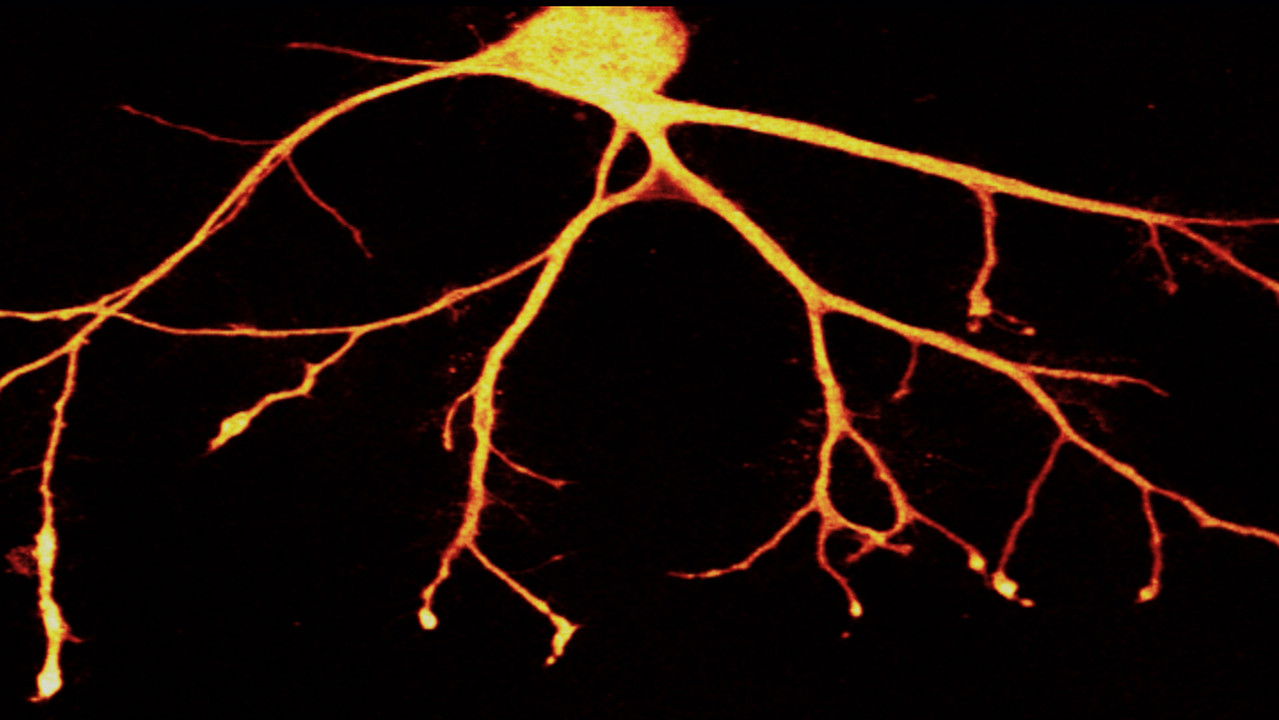

"In Search of Memory" is a very personal portrait of Eric Kandel, the "rock star" of neuroscience and the most important brain researcher of the 20th century. A fascinating documentary about the exciting mystery of the brain which arouses a curiosity in life and learning.